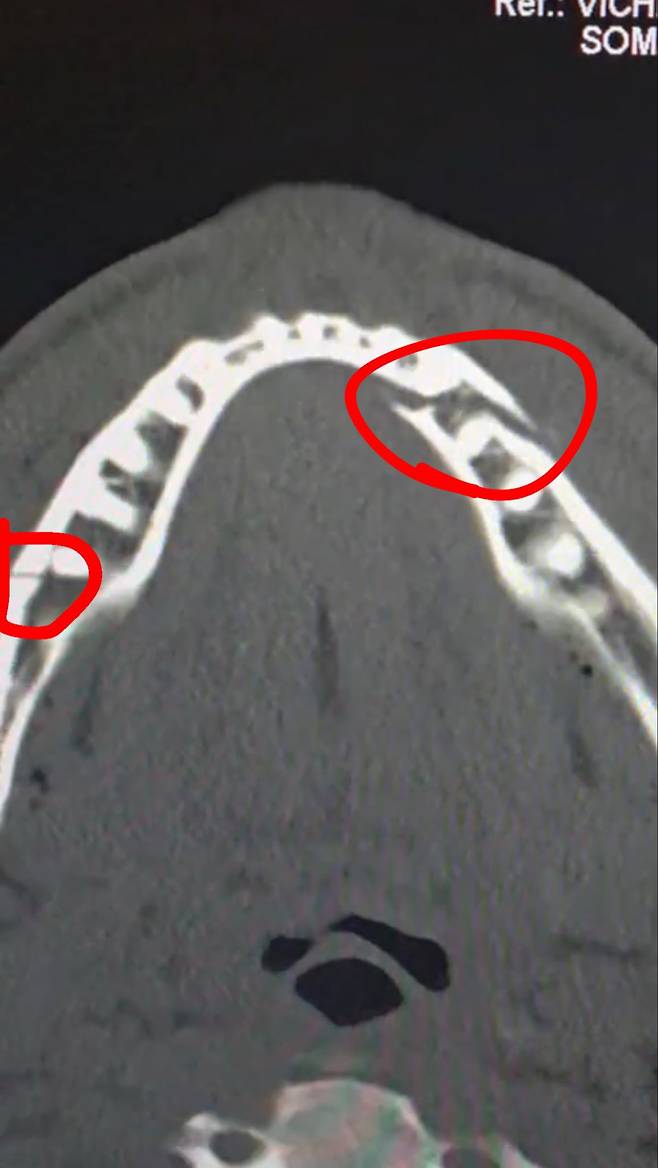

정밀검사 결과 폴의 턱에는 두 군데나 골절이 났다.

게다가 폴은 티타늄 플레이트를 두 개 삽입하고 일부 치아까지 뽑는 수술을 받은 것으로 파악됐다.

폴은 예상보다 오래 버텼지만 실력 차를 극복하지는 못했다. 경기 후 인터뷰에서 그는 "턱이 부러진 것 같다"고 말한 뒤 공식 기자회견에 불참했다. 프로모션 관계자는 "폴이 병원에 입원했지만 직접 차량을 운전해 이동했다"고 전했다.

수술 후 폴은 개인 사회관계망서비스(SNS)를 통해 "수술은 잘 마쳤다. 여러분의 사랑과 응원에 감사드린다"며 "다만 7일 동안 수분에 가까운 유동식만 먹어야 한다"고 알렸다.